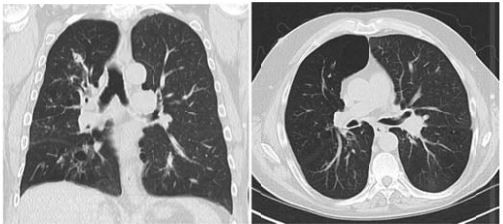

Mulher, 51 anos, caminhada para investigação de pneumonia de repetição. Relata crises compatíveis com asma brônquica, com tosse persistente. Há oito meses apresentou sintomas de dor pleurítica no lado esquerdo, tosse e discreta expectoração, tratada com antibióticos. Há seis meses, radiograma de tórax mostrou infiltrado peri-hilar no pulmão direito e sinais de broqictasia central, tratava com lavofloxacina por 21 dias. Após dois meses, novo estudo radiológico mostrava que o infiltrado permanecia . Antecedentes pessoais: alergia a vitamina B, otite crônica supurativa e hipotireoidismo subclínico. Pneumonia de pulmão D aos 29 anos. Nega tabagismo ou etilismo. Exame físico: sem alterações. Exames laboratoriais: Hemograma: hemoglobina 11 g/dL; hematócrito 35%; leucócitos 9.300/mm³ (60% segmentados, 20 % linfócitos, 7% monócitos, 13% eosinófilos); VHS 53mm. Imunoglobulinas: total 146 mg/dL; IgA 134mg/dL; IgM 153mg/dL; IgG 817mg/dL. Sub-classes de IgG: IgG3 no limite inferior de normalidade. Espirometria: CVF 3.700mL (116%), VEF1 2.600mL (103%), índice de tiffenau de 70%. Tomografia computadorizada de tórax: